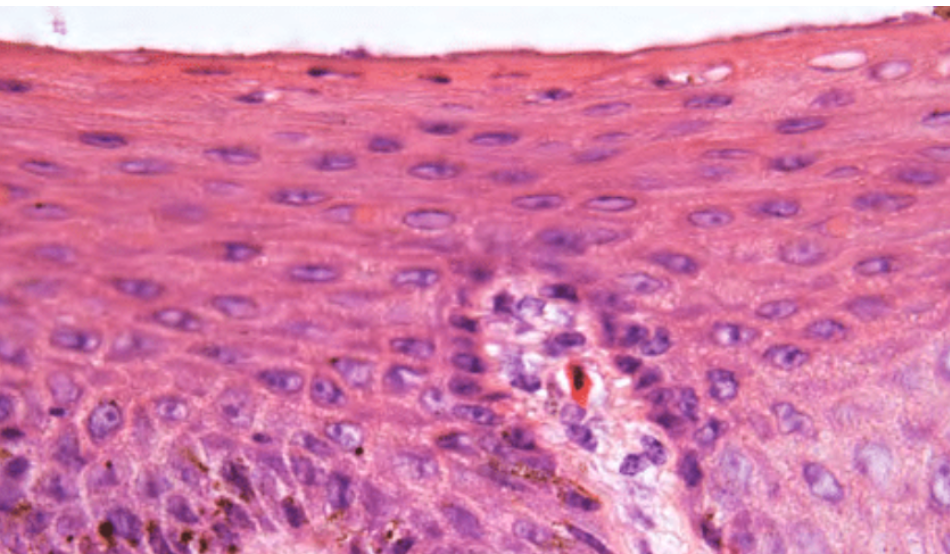

What is this showing?

Epithelium of vagina: stratified squamous non-keritinising